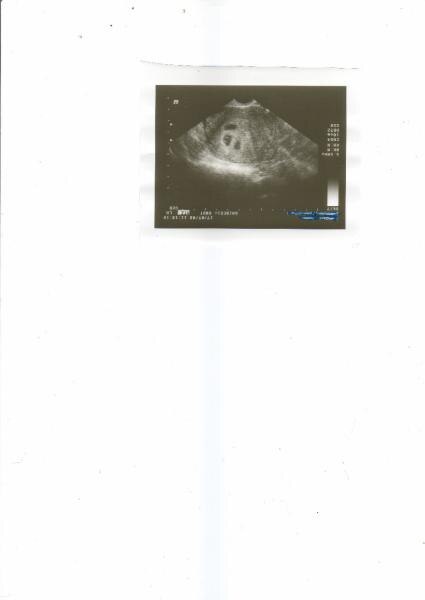

Wie gesagt statt 1x schwarz eben 3x. Aber so sieht das ganze 6+2 aus.

heidernei, sind das zwie in der einen fruchthöhle??? wie viele bekommst denn du??? staun...

Das war jetzt auch mein Gedanke - in der einen Fruchthöhle sind doch zwei helle Punkte zu sehen?! Ich wünsch dir starke Nerven und halt durch bis Freitag!!!

Mach mir keine Angst. das mit den zwei in einer Fruchthöhle hat mein Mann auch schon gesagt. Deshalb hat er auf Zwillis getippt. Mit den anderen beiden konnte er nichts anfangen. Aber beim Ultraschall hat man in jeder Höhle ein Herz gesehen. Hoffe doch nicht, daß in einer jetzt auch noch zwei sitzen. ALARM-bis jetzt sollten es drei sein.Schlimm genug.http://www.rund-ums-baby.de/emoticons.htm?PHPSESSID=0bcb70149428013ee786993a443febd8#

aber so wie die fruchthöhle in der mitte sah es bei meinen eineiigen zwillingsmädels aus... da werden sich doch nicht etwa zwei versteckt haben????!!!! PS: bist du bei einem erfahrenen mehrlingsfrauenarzt? ist ganz wichtig - gerade bei drillies!!!!! lg nadine mit cora & lena *18.7.2005 und lara 25.3.2009

also ich finde nicht das es nach zweien in der Mitte aussieht,man sieht dort einen Dottersack.Es sind dort keine 2 Punkte zu sehen. Bei meinen zweieiigen Zwillingen sah es genauso aus. LG Nadja mit Joelle (*12/2006) + Linnea+Leroy (*2/2009)